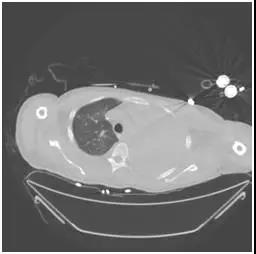

該患者胸部CT(2月20日)